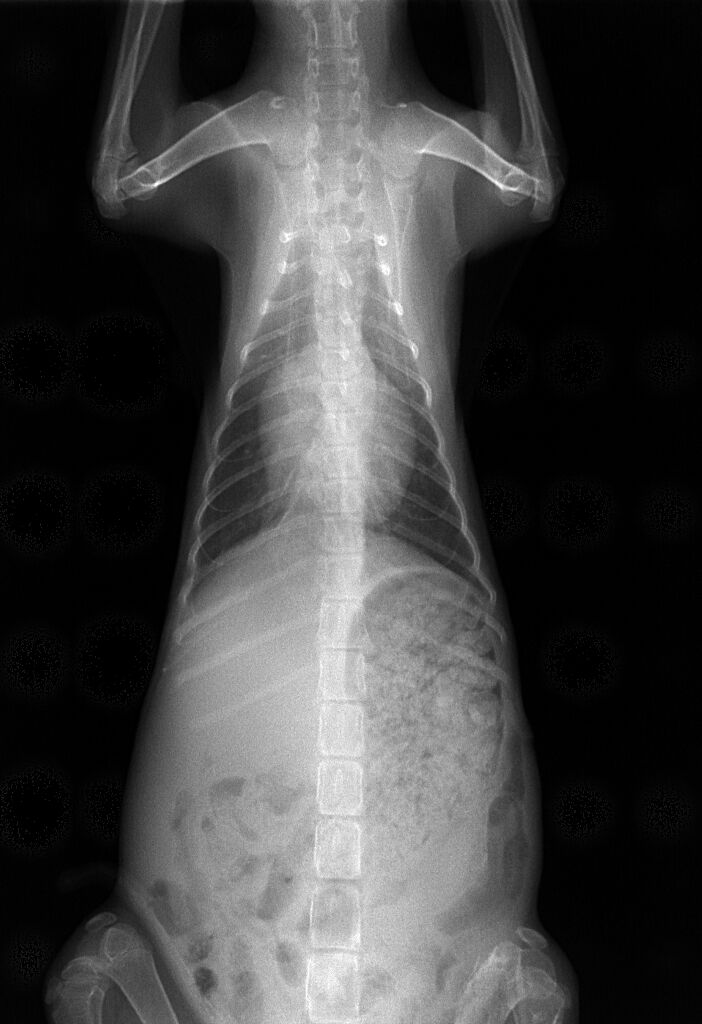

食欲はありませんでしたが、ICU内にて点滴と酸素供給を続け1日、2日と経つうちに徐々に起きている時間が長くなり、3日後には、ICUから出ても呼吸は安定し、食欲が出てきました。7日後にはほぼ正常になり、フードもよく食べて体重もどんどん増えてきました。そこで、レントゲンを撮り、その結果が下の写真です。

押しつぶされて小さくなっていた左の肺はきれいに全体に広がっているのがわかります。これでもう安心できる状態でした。その後、1週間くらい入院して、退院後、先住の他の猫ちゃんとも仲良く、家族のみなさんに大切に育てられています。